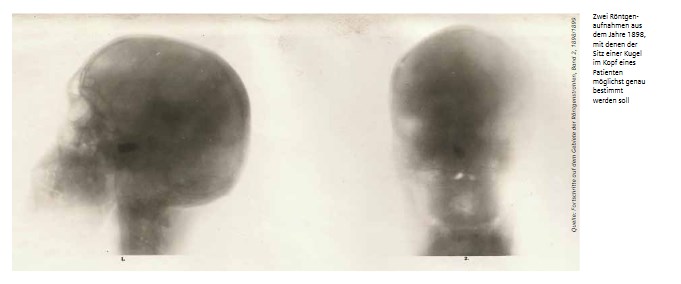

Eigentlich änderte sich das erst durch die Entdeckung der Röntgenstrahlen im Jahr 1895. Doch auch hier gab es keine klare Sicht aufs Gehirn.

Die Aufnahmen des Schädels bilden einen Teil der Röntgengraphie, welcher zu den schwierigsten gehört, schrieb der Röntgenpionier Heinrich Albers im Jahr 1913. Die Knochen des menschlichen Kopfes seien zu dick, um die Röntgenstrahlen in genügender Menge durchzulassen. Dennoch halte ich es durchaus nicht für unmöglich, dass wir bei einer besser ausgebildeten Technik im Laufe der Zeit dahin kommen werden, dass das Röntgenverfahren in der Lokalisation von Tumoren eine Rolle spielt.